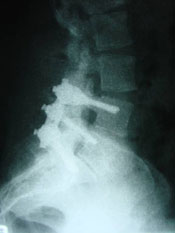

Probably no area of chiropractic spinal manipulation is as challenged as treating the post-surgical patient who is the same, worse, or disenchanted with their surgical outcome. Certainly, the opportunity to treat the patient before surgical intervention is best. When confronted with this post-surgical patient, however, the chiropractic physician proceeds as if with a patient who has not had surgery. i.e. The chiropractor will proceed with the careful history and clinical examination to determine what is causing the pain. That cause may be within the surgical site or adjacent to it. In treating the post-surgical spine, fusion or no fusion is a dictator of care. If there is a fusion, spinal manipulation is given to adjacent levels of the spine to the fused area. If there is no fusion, the doctor carefully proceeds as if no surgery. Some motion may be possible within the spine depending on the surgical procedure performed. (11)